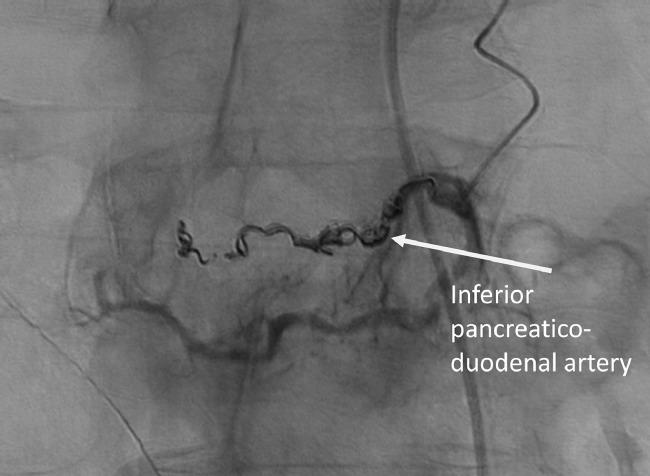

Visceral aneurysms of the pancreaticoduodenal arcades are rare. Although these aneurysms are often asymptomatic and identified incidentally on cross-sectional imaging, aneurysm rupture presents significant morbidity. Ruptured pancreaticoduodenal arcade aneurysms typically present with abdominal pain, hemorrhagic shock, or gastrointestinal bleeding. A 72-year-old male presented with nausea and vomiting and was found to have imaging evidence of duodenal obstruction. This was due to a duodenal intramural hematoma caused by a ruptured submucosal aneurysm supplied by a branch of the inferior pancreaticoduodenal artery in the presence of median arcuate ligament compression of the celiac artery. This was subsequently treated with endovascular embolization with clinical improvement in duodenal obstruction. This case illustrates an unusual presentation of a ruptured pancreaticoduodenal arcade aneurysm.

胰十二指肠动脉弓内脏动脉瘤较为罕见。尽管这些动脉瘤通常无症状,在横断面成像检查时偶然发现,但动脉瘤破裂会导致严重的发病情况。破裂的胰十二指肠动脉弓动脉瘤通常表现为腹痛、失血性休克或胃肠道出血。一名72岁男性因恶心和呕吐就诊,影像学检查发现有十二指肠梗阻的证据。这是由于胰十二指肠下动脉分支供应的黏膜下动脉瘤破裂导致十二指肠壁内血肿,同时存在腹腔干正中弓状韧带压迫。随后对其进行了血管内栓塞治疗,十二指肠梗阻的临床症状有所改善。该病例说明了破裂的胰十二指肠动脉弓动脉瘤的一种不寻常表现。